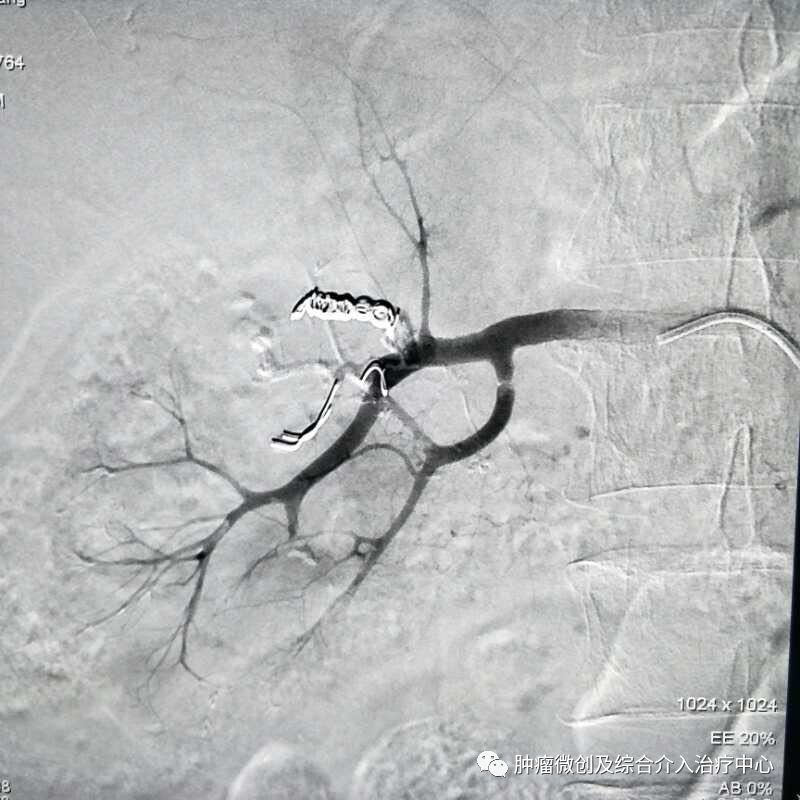

(鼻咽癌颈部转移瘤破溃出血,DSA造影提示左颈部病变血管迂曲、紊乱,内有出血)

(介入栓塞病变血管后,DSA示肿瘤病变血管栓塞好,血管走向清晰,出血停止)项目介绍:头颈部良、恶性肿瘤临床常见,其良性见于鼻咽纤维血管瘤,恶性者见于鼻咽、鼻窦癌,颈部转移性肿瘤等; 传统止血治疗疗效有限,给患者及家属带来极大的精神压力,介入手术栓塞病变血管可达到确切的止血效果,并致病变缺血萎缩。04急性肺栓塞介入手术治疗